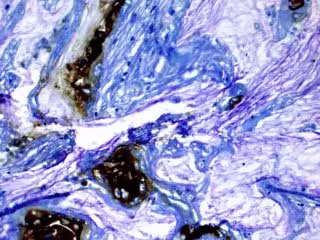

Al analizar el fluido de los quistes en busca de un biomarcador, un anticuerpo llamado mAb Das-1, los investigadores pudieron identificar quistes pancreáticos que probablemente se vuelvan cancerosos con una precisión del 95 por ciento. Las guías clínicas actuales solo son precisas en un 74 por ciento.

El equipo de investigación recolectó líquido de los quistes de 169 pacientes que se sometieron a una cirugía para extirpar los quistes pancreáticos. Los investigadores analizaron el fluido, utilizando una prueba para detectar el biomarcador del anticuerpo Das-1.

En investigaciones anteriores, el biomarcador se había relacionado con quistes pancreáticos en alto riesgo de convertirse en cancerosos. En el nuevo estudio, los investigadores encontraron que el biomarcador era más preciso que cualquier método actual para predecir el riesgo de cáncer en estos pacientes con quistes pancreáticos.